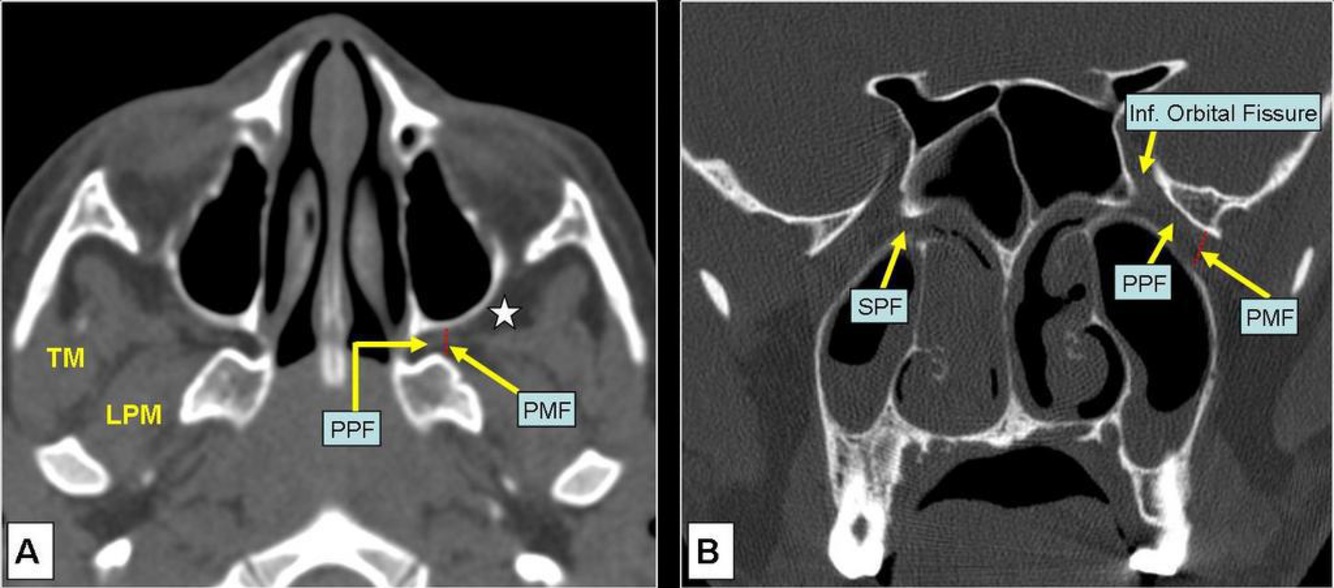

CT/CTA/MRI/MRA of paranasal sinuses, shows a mass with extension into the pterygomaxillary fissure.

Dx?

A

JNA